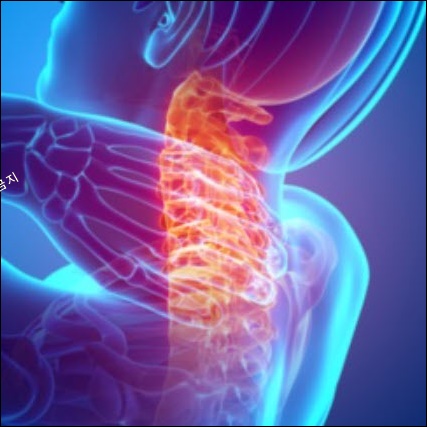

뒷목이 떙기는 질환으로는 크게 '거북목 증후군, 근막통증 증후군, 목디스크'로 3가지가 원인입니다.

#3 목디스크

경추(목뼈)는 총 7개의 뼈로 구성되어 있으며, 경추 사이에 충격을 흡수하는 연골 조직인 추간판(디스크)이 있습니다.

추간판이 후방으로 탈출하면 신경을 압박하여 통증을 유발하게 되는데, 이를 보통 '목 디스크'라고 합니다. 목디스크가 발병하면 목이 상당히 불편하면서 어깨가 아프고 팔다리 저림 증상이 나타나게 됩니다.